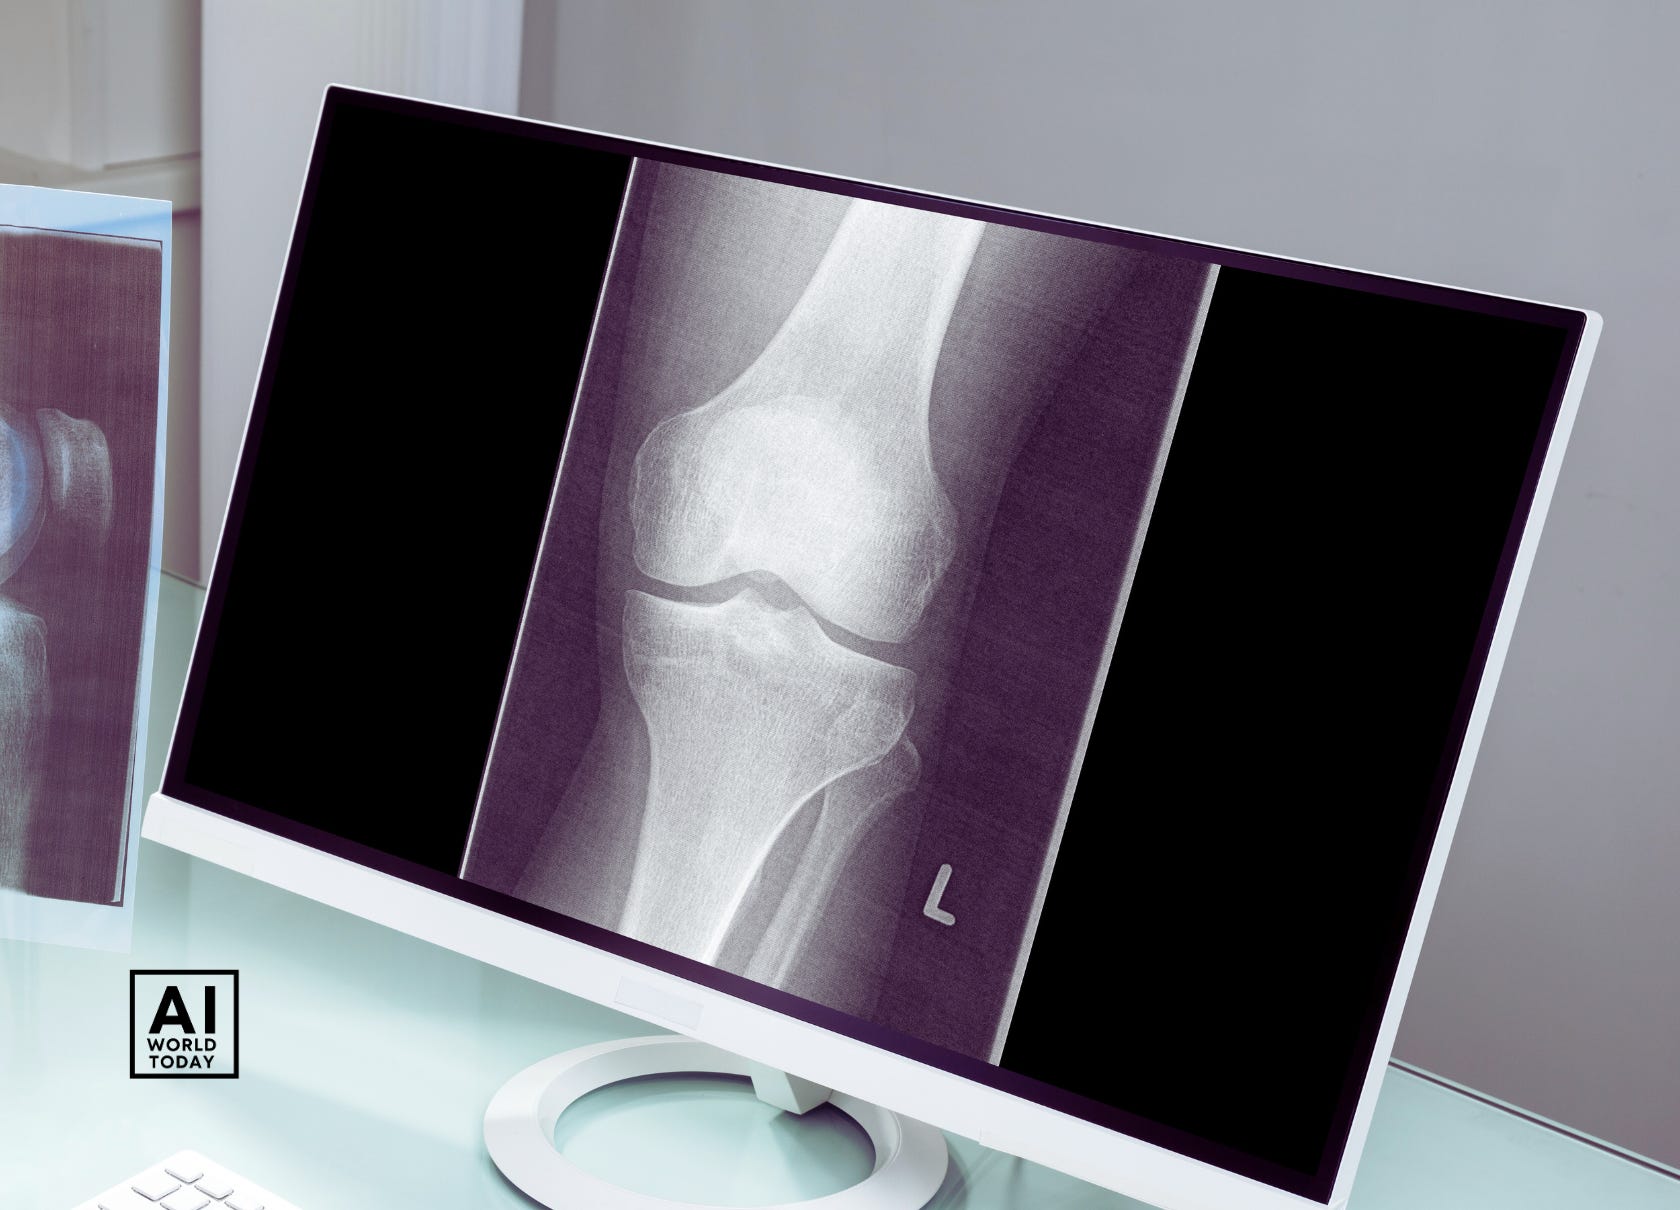

Researchers at the Indian Institute of Technology Guwahati have developed an artificial intelligence-based model named OsteoHRNet that can assess the severity of Knee Osteoarthritis from X-ray images. This could help doctors detect the condition at an early stage for better management.

Knee Osteoarthritis, a degenerative joint disease, affects 28% of the Indian population. Early diagnosis is crucial to manage pain and slow progression, but expensive tests like MRI and CT scans are not widely accessible. X-rays, though more economical and available, rely on clinical evaluation for diagnosing osteoarthritis.

The IIT Guwahati team built OsteoHRNet using High-Resolution Network, an efficient deep convolutional network. The model predicts severity according to the World Health Organization's Kellgren and Lawrence grading scale of 0 to 4 - from low to high severity.